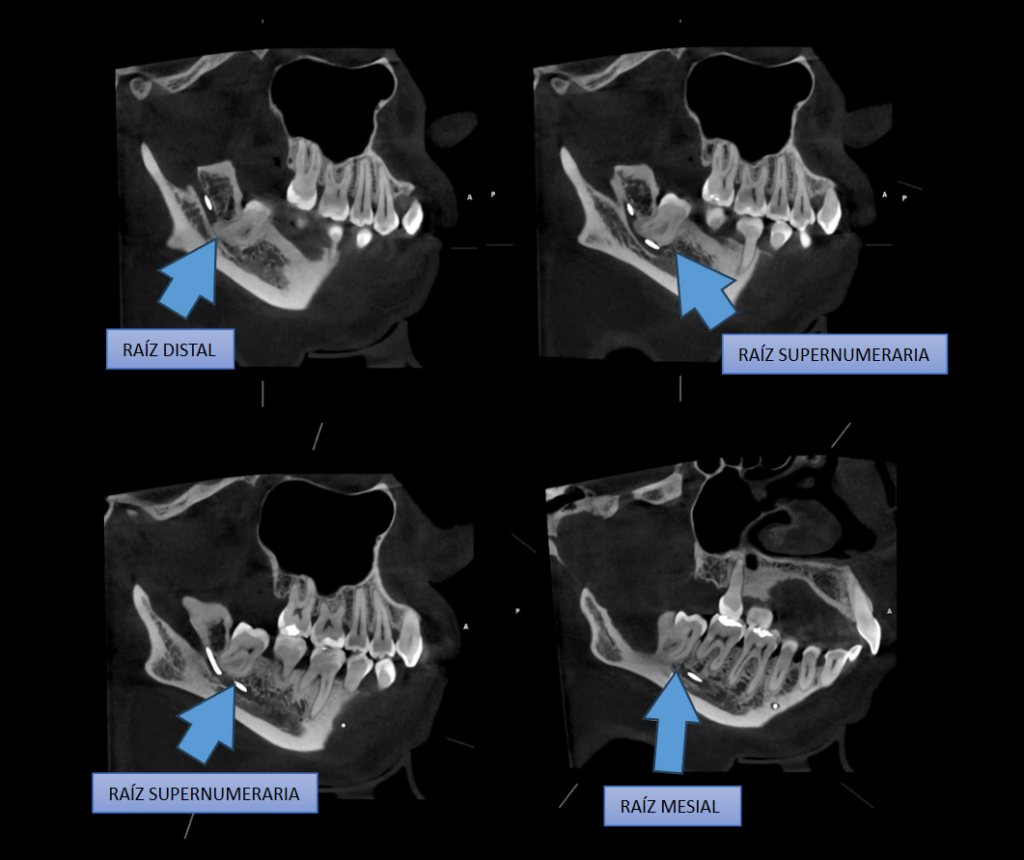

A la evaluación de la tomografía computarizada del motivo de consulta que fue la pieza 48 se observa impactada contra la superficie cervicodistal de la pieza 47, asimismo se observa la presencia de una raíz supernumeraria por vestibular y por mesial (paramolaris), la

hipercementosis de los tres segmentos, así como la dilaceración de los mismos a predominio de la raíz supernumeraria. Finalmente, el conducto dentario inferior recorre por lingual de la raíz distal y por el medio de ambas raíces mesiales, contactando con los ápices.

CORTES TRANSAXIALES